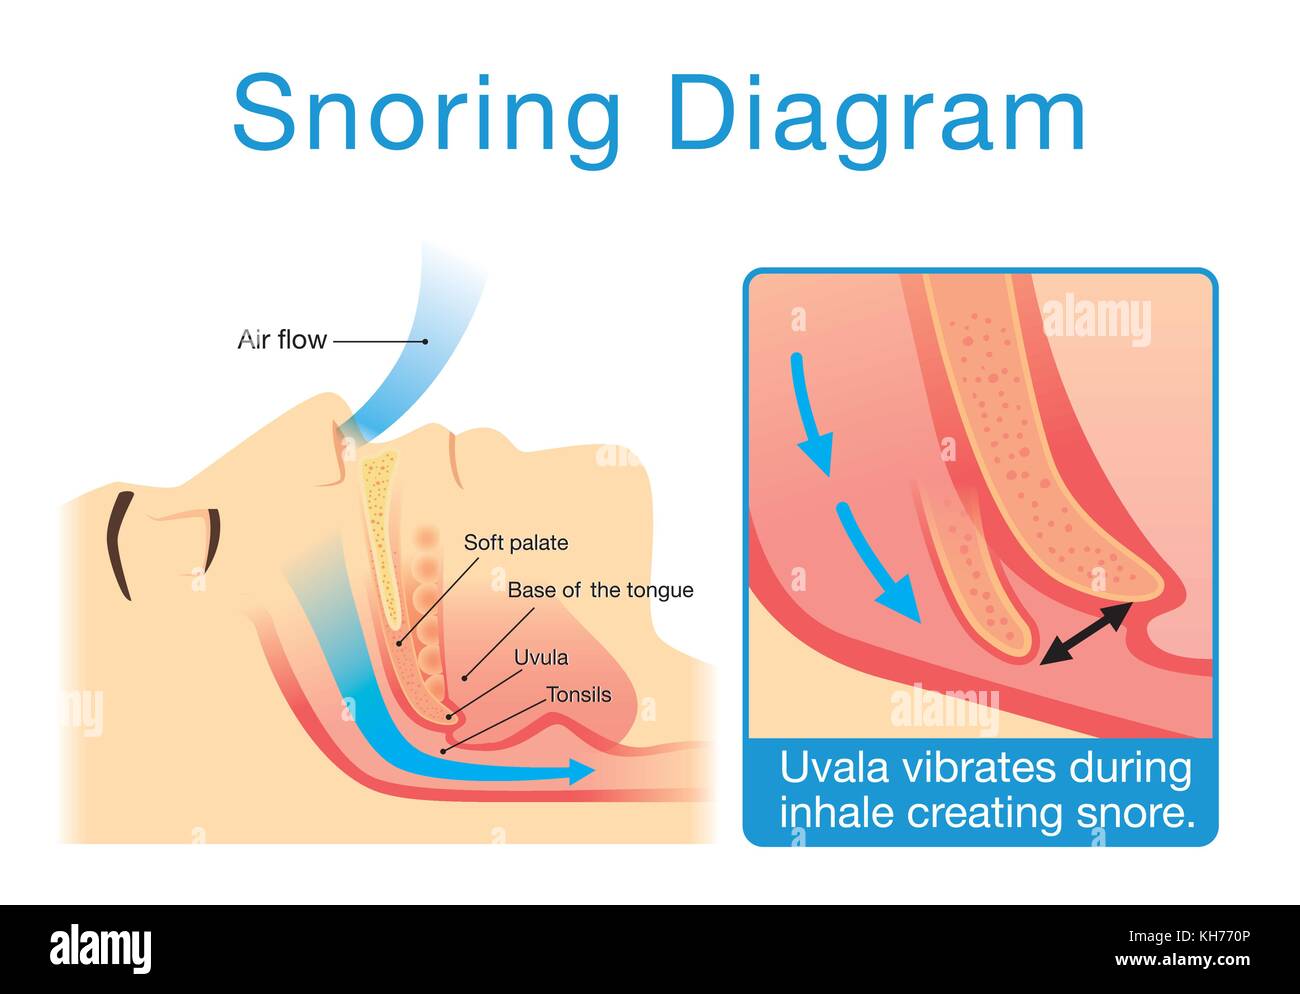

Anatomy of human upper airway while sleeping with snoring. Stock Vectorhttps://www.alamy.com/image-license-details/?v=1https://www.alamy.com/stock-image-anatomy-of-human-upper-airway-while-sleeping-with-snoring-165501638.html

Anatomy of human upper airway while sleeping with snoring. Stock Vectorhttps://www.alamy.com/image-license-details/?v=1https://www.alamy.com/stock-image-anatomy-of-human-upper-airway-while-sleeping-with-snoring-165501638.htmlRFKH770P–Anatomy of human upper airway while sleeping with snoring.